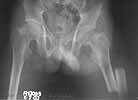

We managed to get neutral phosphate, initiated medical treatment and did an antegrade SIGN nailing of left femur along with couple of screws to neck using miss a nail technique. He complained of pain of the right femur and both forearms. In OT these areas were screened using image intensifier and found that he has looser zones of all these with impending fractures. Yesterday we did a retrograde nailing of right femur usingSIGN nail. Both ulnas were stabilised usingLambrudini wires in a closed fashion. All fractures and looser zones were stabilised by closed surgery using image intensifier. It may be interesting to see the post of picture of both the hips in which one side shows an antegrade femoral SIGN nail and the other side shows a retrograde SIGN nail.